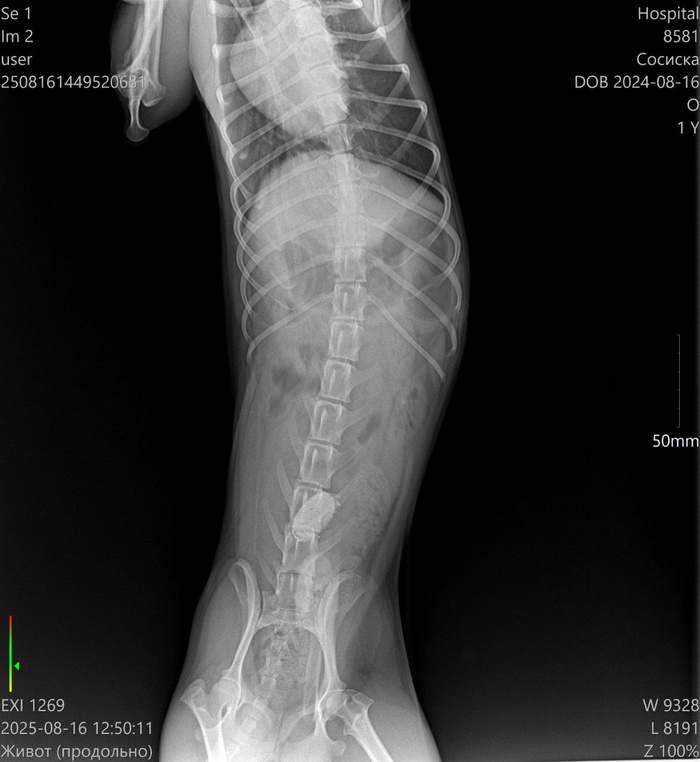

Краткое содержание для ЛЛ: такса сожрал какую-то пробку и через некоторое время у него начались проблемы. Спасибо ветеринарам: таксу - подкромсали, ненужное - убрали, нужное - оставили.

Ветеринарная клиника: измерение температуры, сделали УЗИ - в желудке обнаружена какая-то инородная штука, или показалось или... завтра на операцию.

Клизмы и прочие смазки не уговорили отдать то ли крышку, то ли ещё что-то такое металлическое.

Врачам пришлось резать сосиску и извлекать инородное тело.